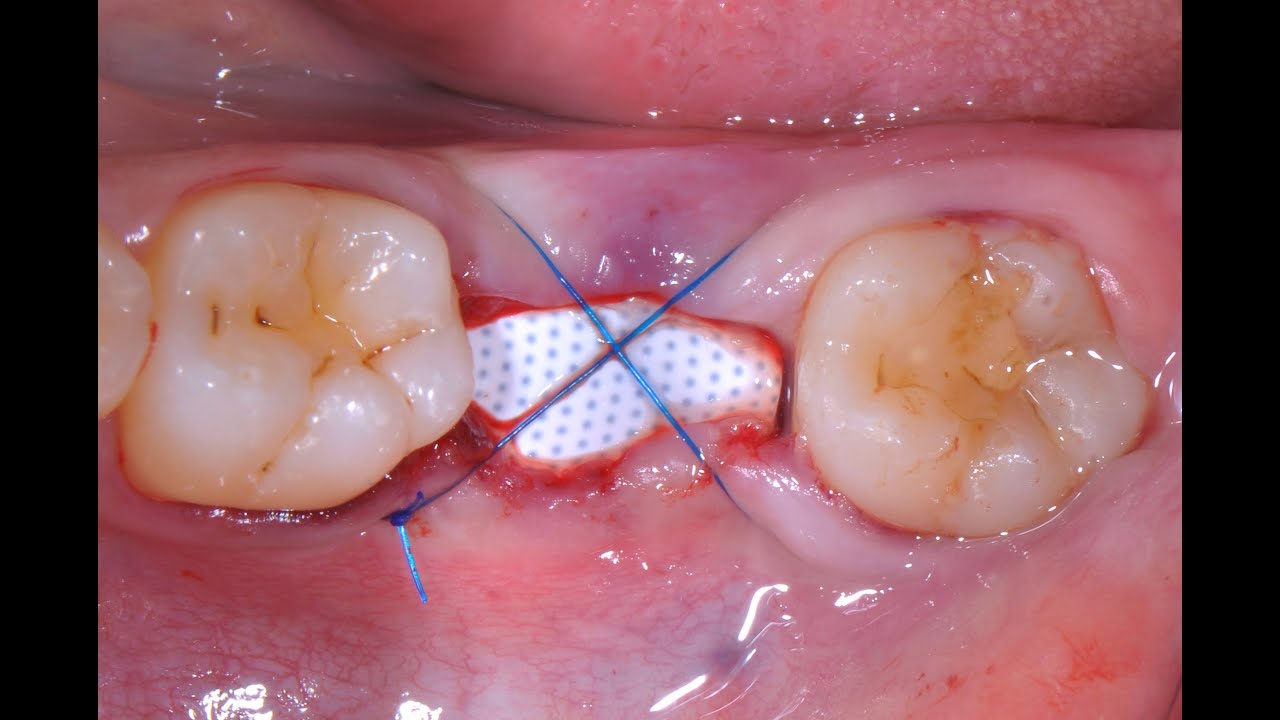

Las membranas CYTOPLAST® TXT-200 son unas membranas no reabsorbibles de PTFEd (politetrafluoroetileno denso), especialmente indicadas para defectos óseos donde se requiera un efecto barrera prolongado, incluyendo preservaciones alveolares unitarias. Cabe destacar que esta membrana se puede dejar intencionadamente expuesta, lo que permite ser retirada sin tener que realizar una cirugía. Ésta es la conocida Técnica de Preservación Alveolar CYTOPLAST®, puedes consultar aquí su protocolo.

Además, las CYTOPLAST® TXT-200 son totalmente oclusiva a las bacterias y pueden ser fácilmente recortadas, tanto el PTFE como el propio titanio. Se adaptan a todos los contornos del tejido gracias a su demostrable y notable flexibilidad, al igual que todas las otras membranas de la gama CYTOPLAST®.

Estas membranas están diseñadas para incrementar la estabilidad del injerto, mediante un entramado hexagonal (superficie texturizada RegentexTM ), que aumenta la superficie real para adhesión celular sin aumentar la porosidad.

- Membrana no reabsorbible diseñada para soportar la exposición.

- Puede ser retirada no quirúrgicamente cuando se deje expuesta.

- Es impermeable a cualquier bacteria.